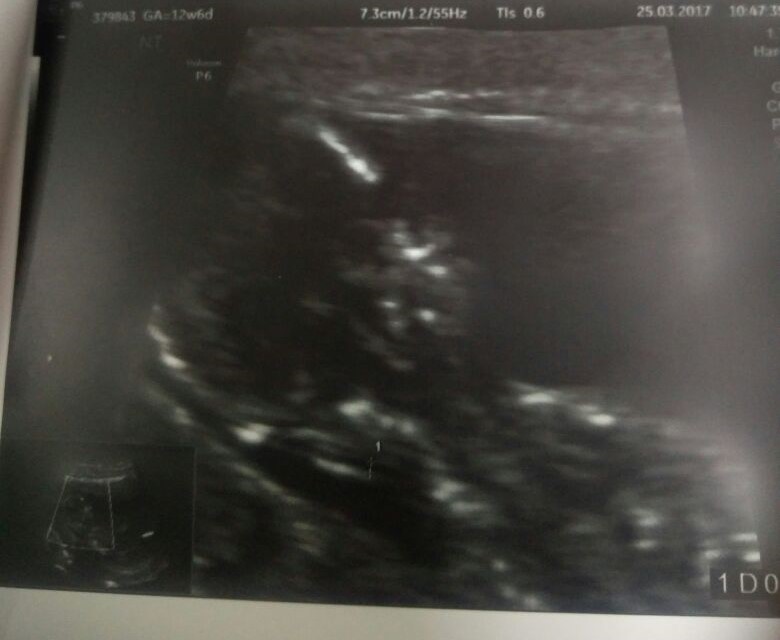

This is my baby's ultrasound taken on 12 Weeks 6 Days. Kindly provide your predictions.